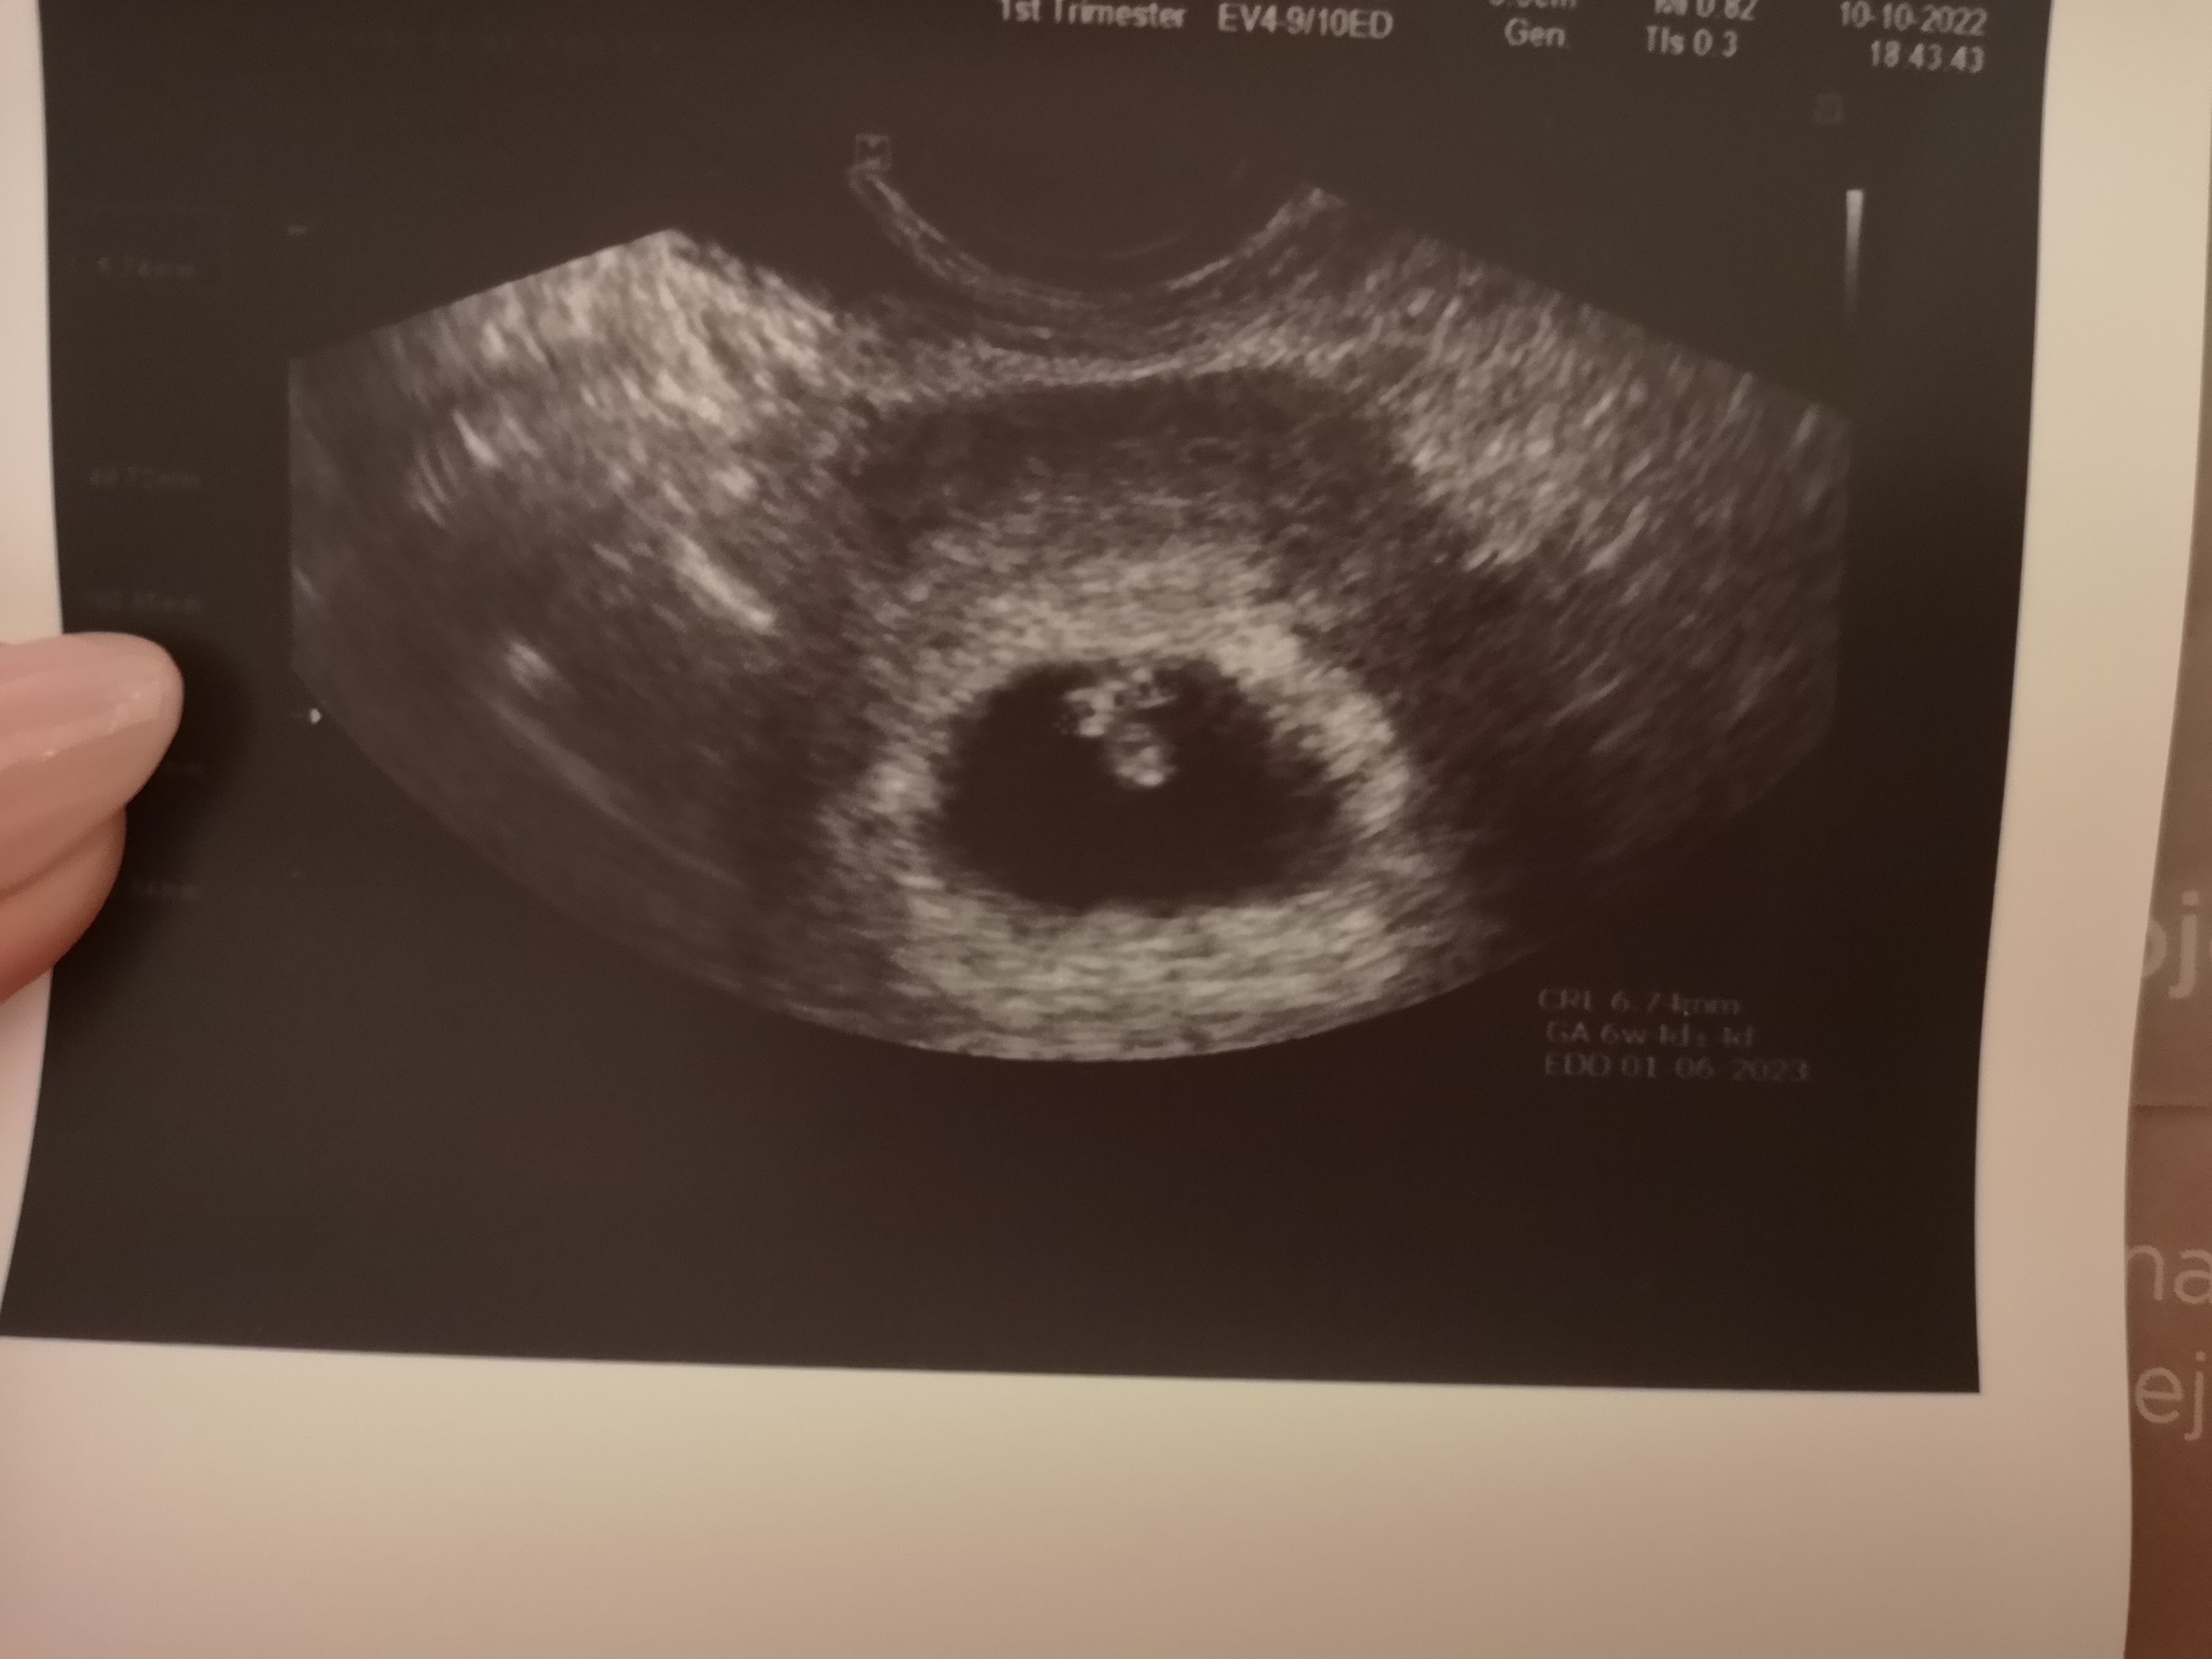

Cudowna wiadomość ❤Ja już po wizycie. Widziałam bijące serduszko. Zarodek 4 mm6 tydzień

Kiedy kolejna wizyta ?Takto mój okruszek tydzień temu i dziś

Bardzo się cieszę, że u was wszystko okJa już po wizycie. Widziałam bijące serduszko. Zarodek 4 mm6 tydzień